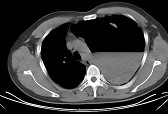

- 单项选择题女,6岁, 胸闷,咳嗽, 胸部CT如图,最可能的诊断为 ( )

A、畸胎瘤

B、右侧液气胸

C、右肺肺大疱

D、右侧脓胸

E、支气管囊肿并感染